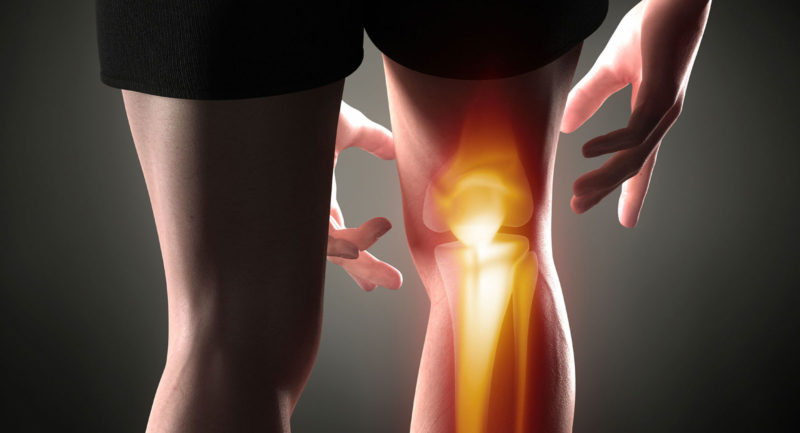

На первый взгляд, артроз и артрит очень похожи, однако эти заболевания существенно различаются. Сегодня мы расскажем о том, каковы симптомы этих недугов и какие методы профилактики помогут предотвратить болезнь.

И при артрите, и при артрозе происходит поражение суставов, однако это разные заболевания. Если при артрозе поражаются только суставы, то артрит подразумевает воспалительный процесс во всем организме. Воспаление может быть вызвано инфекцией, отклонениями в работе иммунной системы или же нарушением обмена веществ. Поэтому при данном заболевании часто страдают не только суставы, но и внутренние органы – печень, почки, сердце.

Симптомы артроза и артрита

Это один из главных признаков артроза и артрита, однако характер боли у данных заболеваний отличается. Так, при артрозе боль проявляется в основном только при движении и сильной дополнительной нагрузке, при этом, она может быть не очень сильной (особенно на первой стадии заболевания). Именно поэтому часто люди и не придают ей значения, запуская болезнь. На второй стадии боль проявляется уже при небольшой нагрузке, а на третьей – даже в состоянии покоя. Однако она может стихнуть, если человеку удается занять удобное положение.

А вот в случае артрита боль в покое не утихает. Особенно характерны для артрита ночные боли – между тремя и пятью часами утра.

Хруст при артрозе возникает из-за того, что разрушается хрящевая прослойка и происходит трение костей. Однако если у вас иногда хрустят суставы, то это не повод для паники. Хруст при артрозе имеет специфический звук: это не легкое пощелкивание, а грубое, сухое. Чем выше стадия, тем сильнее хруст в суставе.